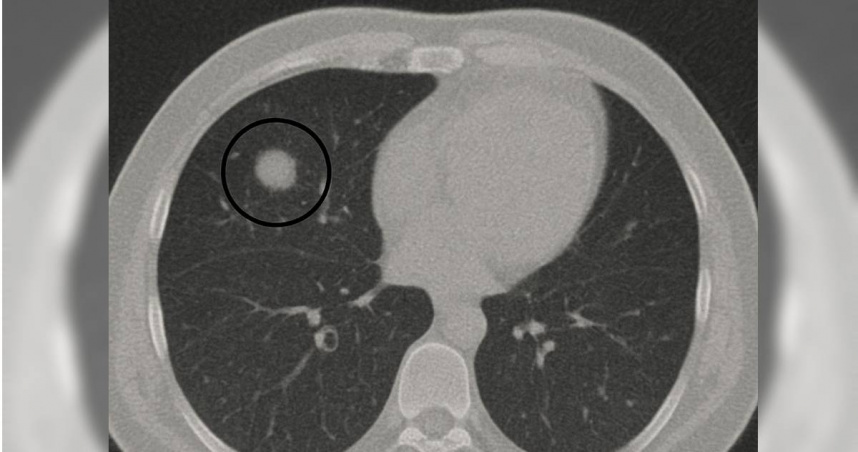

劉博仁醫師指出,部分肺結節可能只是暫時性的發炎反應,但也可能是早期癌症的警訊。(圖/翻攝自Facebook/劉博仁營養功能醫學專家)

「肺結節」是早期癌症的警訊?營養功能醫學專家劉博仁分享2個病例解釋,1位因發炎造成的假性結節而免於開刀,另一位則及早發現第一期肺腺癌並成功切除。他提醒大眾,肺結節可能是暫時發炎也可能是癌症警訊,低劑量電腦斷層是重要篩檢工具,並強調飲食、生活習慣與及早追蹤,對維護肺部健康的重要性。

營養功能學名醫劉博仁今(2日)在臉書粉專發文分享2個真實病例,提醒大眾面對肺部結節時應保持警覺,但也不要過度恐慌。首先,第一位病患在醫院進行低劑量電腦斷層(LDCT)檢查時,發現肺部有一個1.2公分的不規則結節。

對此,劉博仁醫師強烈建議立即開刀,但病患猶豫不決,最後選擇先以功能醫學調理並密切追蹤。4個月後再檢查,結節縮小到僅剩0.3公分,最終確認只是因感染造成的假性結節,幸運地避免了不必要的肺部手術。

另一位病患則是女性,右上肺發現0.9公分的毛玻璃樣結節。起初半年間形狀沒有變化,但隨後逐漸長大。劉博仁醫師強烈建議手術,病理結果證實為第一期肺腺癌。由於及早發現與處理,成功切除且沒有擴散,病患因此保住了健康。

劉博仁醫師指出,這2個截然不同的結果提醒人們,部分肺結節可能只是暫時性的發炎反應,但也可能是早期癌症的警訊。

劉博仁醫師強調,LDCT是目前最有效的早期肺癌篩檢工具,能夠發現小於1公分的結節,遠優於傳統胸部X光。醫師會根據國際Fleischner指南與臨床經驗來判斷是否需要手術,若結節大於8毫米且形狀不規則、毛玻璃樣結節持續增大、出現明顯實性成分,或病患屬於高危險族群,就應積極處理,以免錯過治療時機。